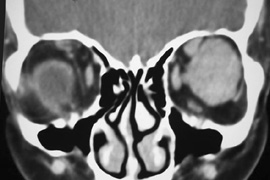

Valuable information about the nature and extent of an orbital pathologic process is provided by imaging studies such as computed tomography (CT) scan, magnetic resonance imaging (MRI), and orbital echography. Better spatial resolution, ready accessibility, and lower cost make CT the preferred choice for orbital imaging in most cases. Orbital fat provides a natural contrast between most adjacent orbital structures on CT scanning, and orbital bones are visualized well. Computed tomography is essential for evaluation of the orbital bones because they cannot be imaged with MRI. Direct coronal or sagittal images are important to identify the relationship of a lesion to the optic nerve so that the surgical approach can be planned to avoid traversing the optic nerve (Fig. 1).

Fig. 1. A. Axial CT scan demonstrating a large, well-encapsulated lesion in the orbital apex. Coronal (B) and sagittal (C) scans demonstrate that the mass lies inferior and medial to the optic nerve within the intraconal space. This information is useful in planning the surgical approach to the mass, which should avoid traversing the optic nerve.